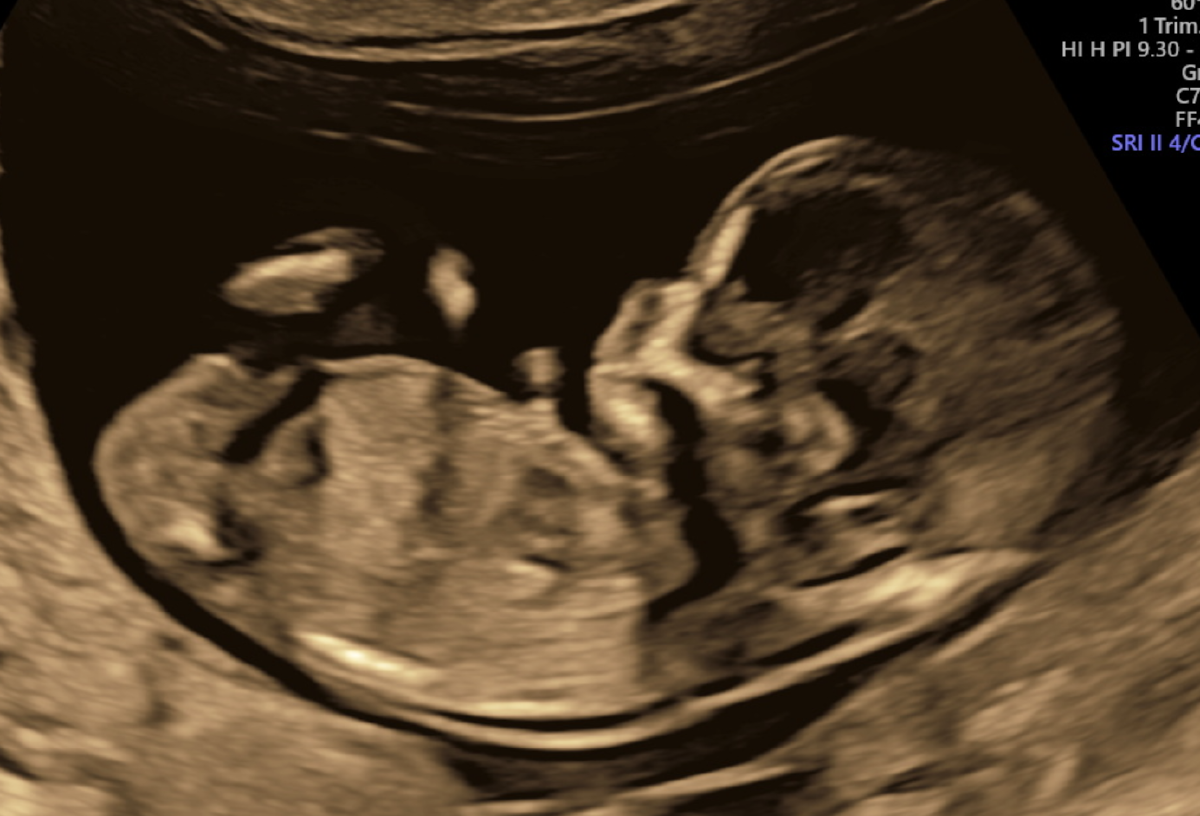

Bedroefd gaan we terug naar Gemert, om het nieuws te delen, en onze zoon op te halen. Het is een warme dag, en mijn ouders zitten buiten in de tuin. Op zeker moment laat mijn moeder de opmerking vallen wat er nu moet komen van onze kinderwens voor een tweede kind. Op dat moment kijken Heleen en ik elkaar aan. En besluiten dan maar mee te delen dat Heleen op dat moment al negen weken zwanger is. En we halverwege december ons tweede kind verwachten (codenaam Poetje). Een groter cadeau hadden we ons niet kunnen wensen! En wat een liefde en positiviteit geeft dat ook, zoals Tuur dat ons ook geeft door rond te dartelen, en geen idee te hebben van wat er gaande is. En ons daarmee zoveel helpt. We hebben daarbij gewoon rust en regelmaat, en moeten door.